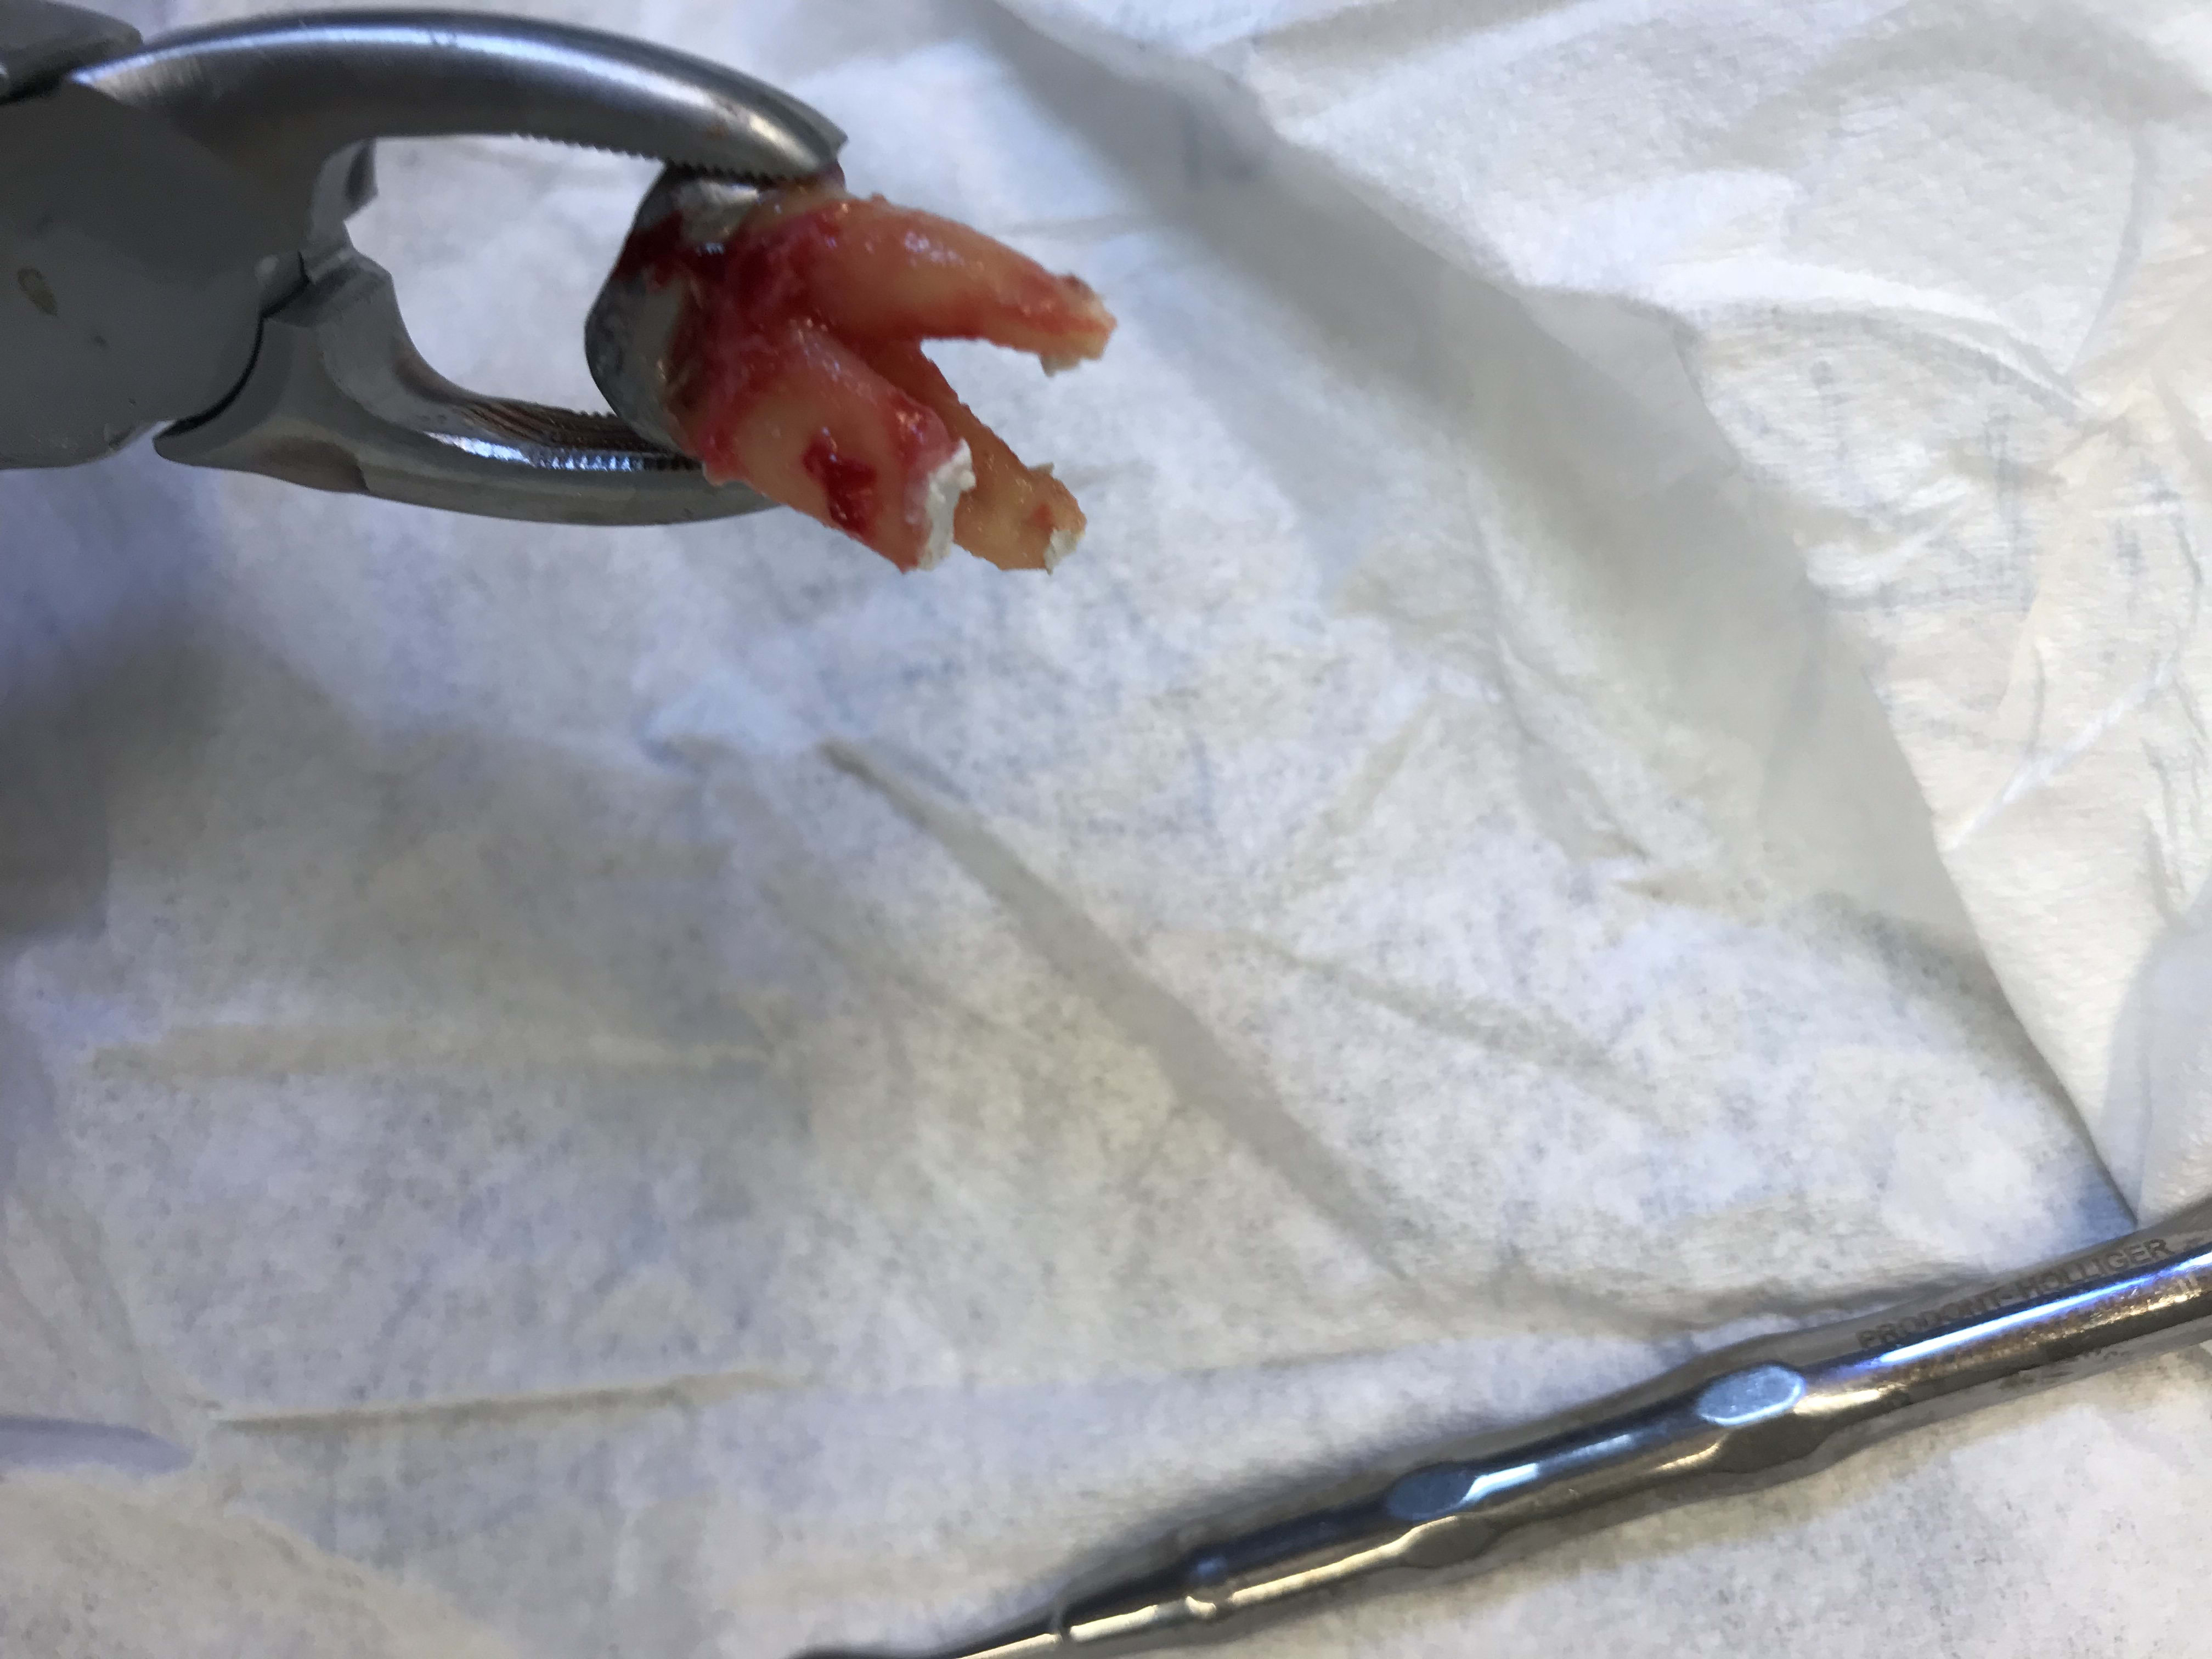

- du coup j’extrais la 26 et en même temps j’en profite pour faire une ERI sur 27

tu as nettoyé le haut des racines ou meme pas ?

Juste un curetage alvéolaire